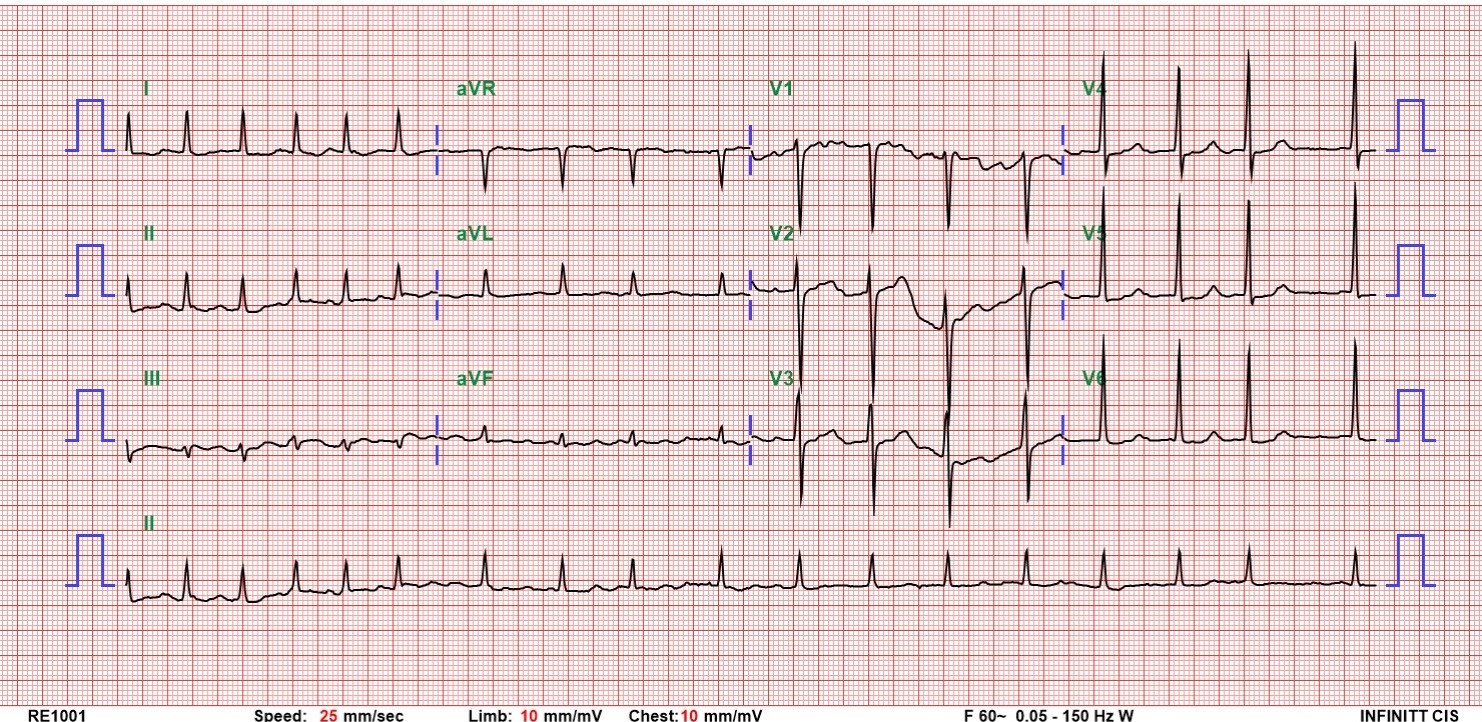

Relevant Test Results Prior to Catheterization

A chest X-ray revealed bilateral pulmonary edema and pleural effusion. The EKG showed atrial fibrillation with non-specific ST-T changes. Cardiac enzymes peaked at hs-Troponin I of 13,591 pg/ml. The patient was admitted to the cardiac intensive care unit with a tentative diagnosis of NSTEMI.